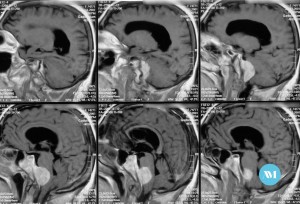

Los meningiomas son tumores que se generan a partir de la duramadre (membrana que recubre el cerebro). Se puede localizar en cualquier zona, por lo que son muy variables los síntomas que pueden localizar en cualquier zona, por lo que son muy variables los síntomas que pueden llegar a dar, Crecen de forma muy lenta, incluso a lo largo de muchos años, desplazan el cerebro pero no lo suelen invadir (extraparenquimatosos y expansivos) y, al ser de crecimiento muy lento, pueden llegar a alcanzar gran tamaño porque el cerebro se va adaptando sin dar síntomas clínicos.

Los meningiomas son tumores benignos, siendo muy raro que se malignicen. La localización mas frecuente es en la convexividad del cráneo pero también se puede situar en la base del cráneo, siendo esta zona mas complicada para su extirpación completa dado que pueden estar adheridos o envolviendo estructuras tan importantes como arterias, nervios craneales o tronco cerebral.

Observación: Los tumores pequeños en pacientes de edad avanzada que no causan síntomas pueden ser seguidos con imágenes por resonancia magnética. Dado que estos tumores son benignos y de crecimiento lento y que pueden no causar ningún problema durante la vida de algunos pacientes.